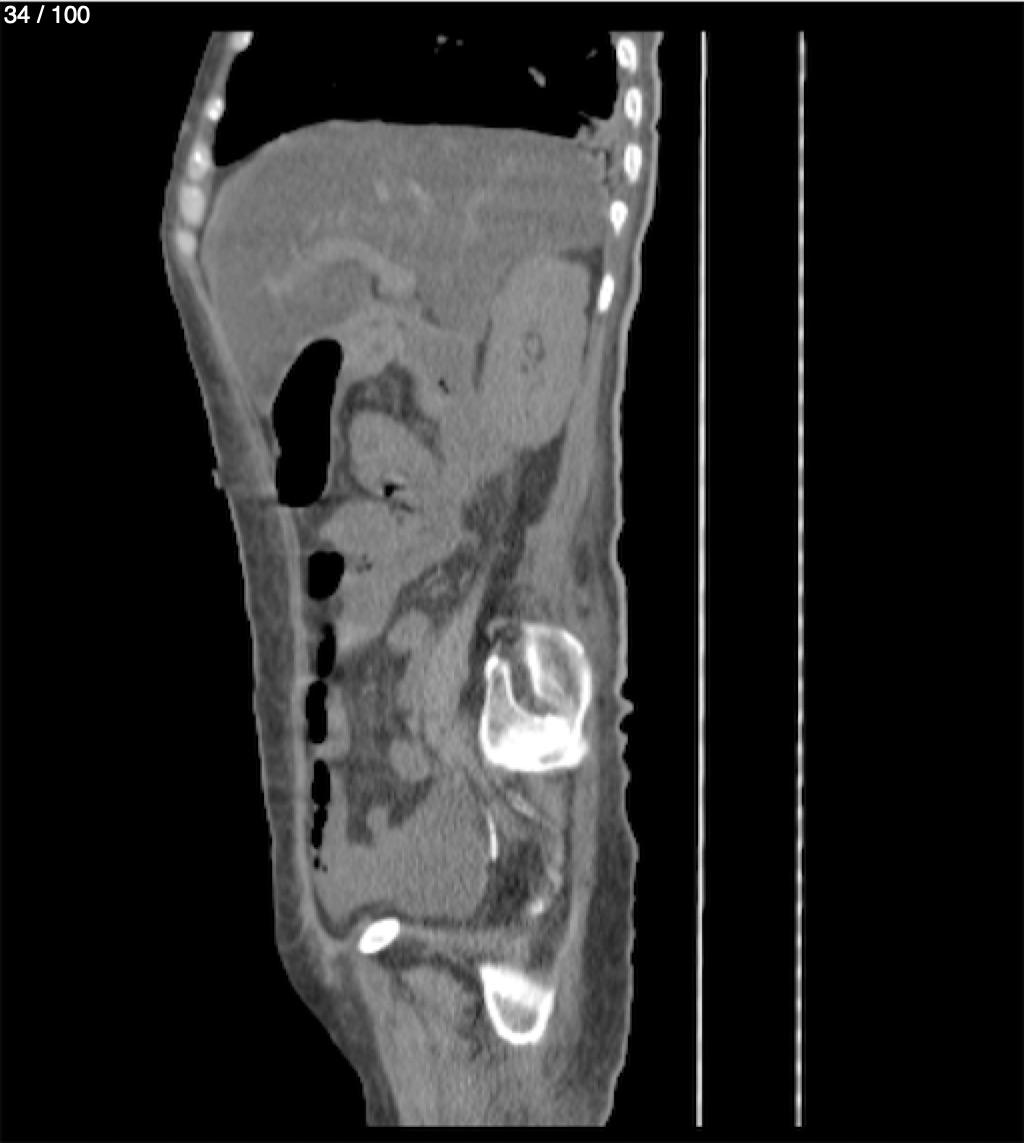

Hilda Geronimo Mendez 60A - T.C Abdomen Simple